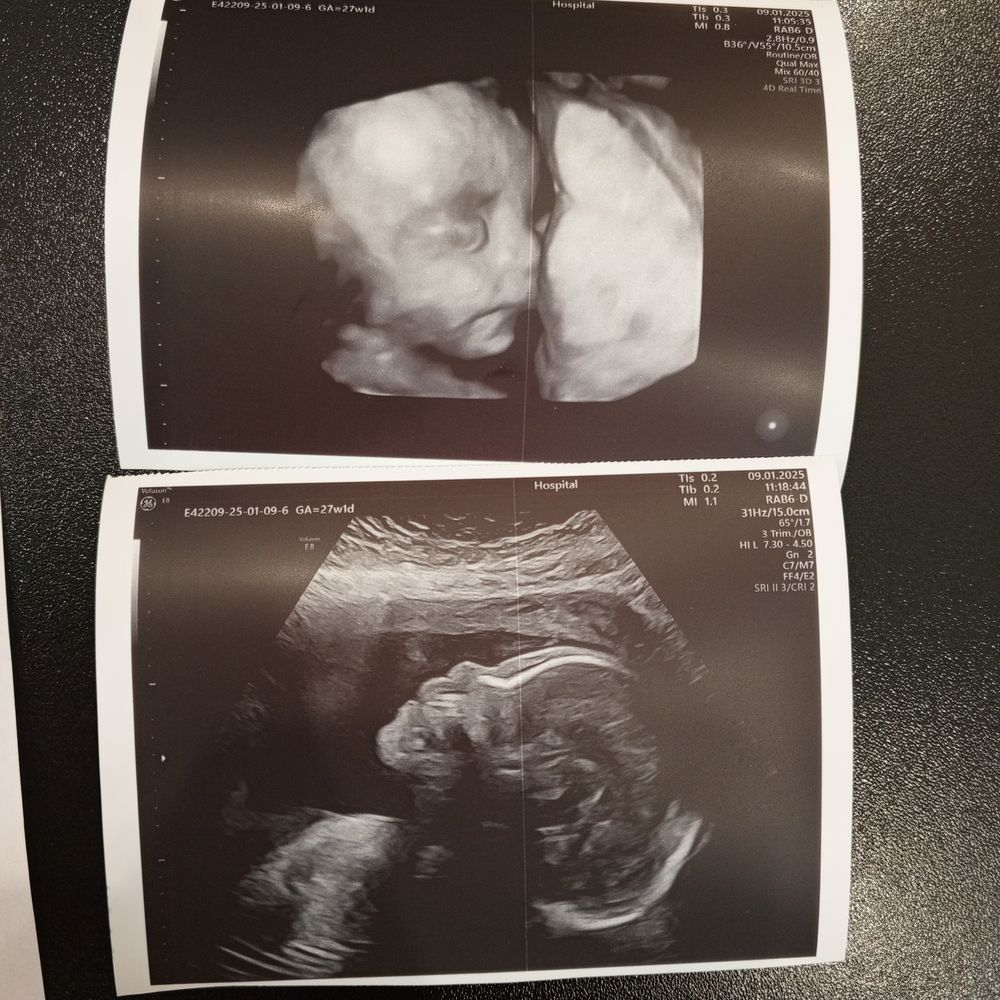

Наши будни, наши неделькиПрошло чуть больше месяца с последнего поста. За это время я дважды повторила эхокг и наконец то врач поставила точку. Сердце в норме настолько, насколько возможно. Остальное будет ясно уже после рождения. С того времени как малышка стала активно стабильно шевелится я поуспокоилась, и теперь реже хожу на узи. Доча растет и развивается нормально, никаких отклонений от нормы пока больше не выявлено, весит чуть больше 800гр +-100гр. Рр грыжи на данный момент 37х37. В остальном все без отклонений. Смотрели сегодня и в 3д, малышка пошла в папу и очень похожа на своего двоюродного братика.